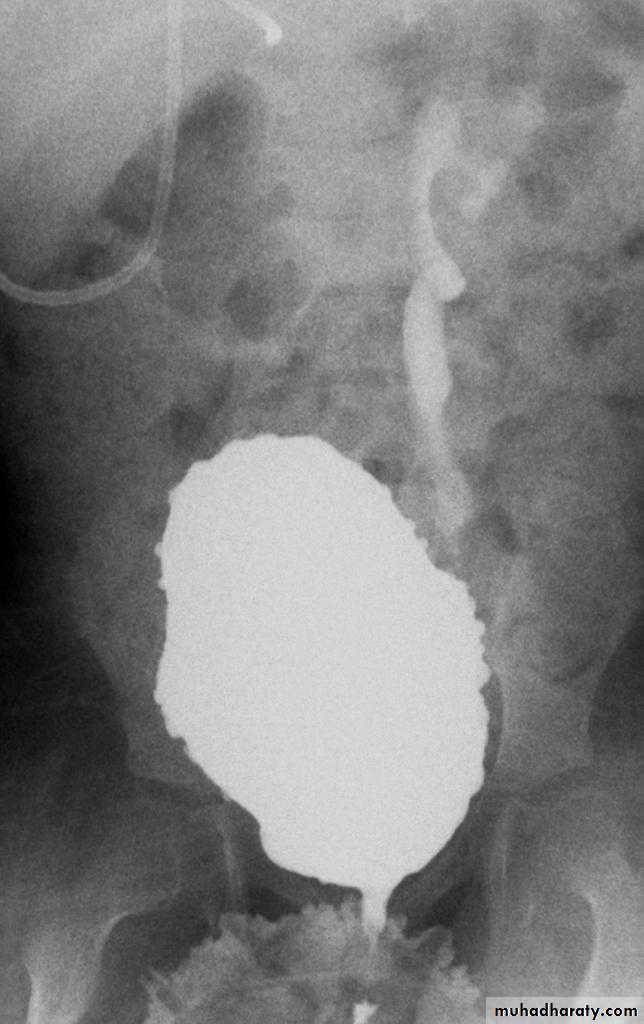

Wilms Tumor ;Nephroblastomma

Most common malignant abdominal neoplasm in children.Peak age: 2-3 years.

It arise from kidney, 90 % unilateral, 10 % bilateral.

Clinical presentation: Palpable abdominal mass, hypertension or hematuria.

Radiological features:

Appear as soft tissue opacity on plain x ray displacing the bowel loops.

On CT scan appear as a large heterogeneous well defined solid mass.

Sometimes there is a calcification and cystic formation.It cause displacement of adjacent structures and may cross the midline.

Treatment: surgery and radiotherapy.

Prognosis: cure rate about 90 %